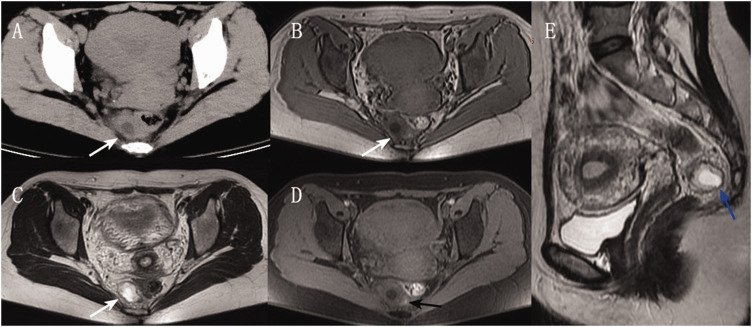

腹膜后异位妊娠是一种极为罕见的异位妊娠,由于严重的腹腔出血,可能危及生命。腹膜后异位妊娠因其不典型的位置和非特异性的症状而经常被误诊。据我们所知,迄今为止还没有报道过定位于肠系膜的异位妊娠病例。在这里,我们提出的情况下,在她的35岁左右的妇女腹膜后异位妊娠定位于肠系膜。由于症状不典型,最初被误诊为肠胃炎,导致治疗延误。本研究旨在提高医师对直肠系膜异位妊娠的认识。

Retroperitoneal ectopic pregnancy is an extremely rare form of ectopic pregnancy that can be life-threatening due to severe intra-abdominal hemorrhage. Retroperitoneal ectopic pregnancy is frequently misdiagnosed because of its atypical location and nonspecific symptoms. To the best of our knowledge, no previous cases of ectopic pregnancy localized to the mesorectum have been reported to date. Here, we present the case of a woman in her mid-30s with retroperitoneal ectopic pregnancy localized to the mesorectum. The condition was initially misdiagnosed as gastroenteritis due to atypical symptoms, which resulted in delayed treatment. This study aimed to improve the clinical recognition of mesorectal ectopic pregnancy among physicians.